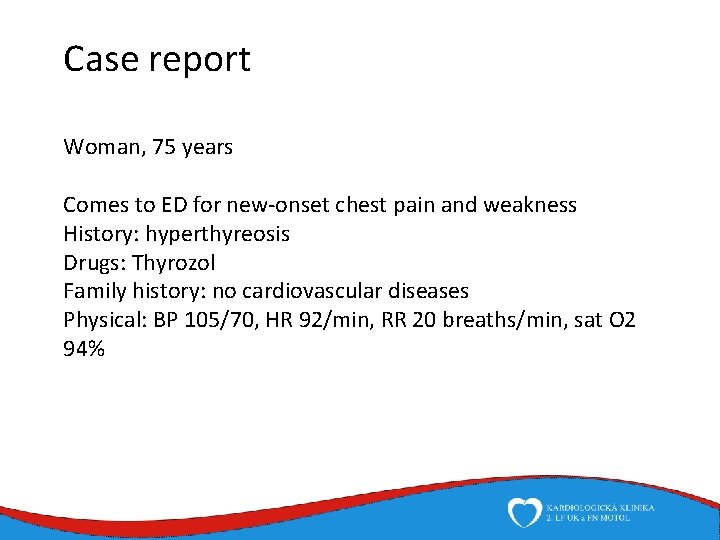

Case report Woman, 75 years Comes to ED for new-onset chest pain and weakness History: hyperthyreosis Drugs: Thyrozol Family history: no cardiovascular diseases Physical: BP 105/70, HR 92/min, RR 20 breaths/min, sat O 2 94%